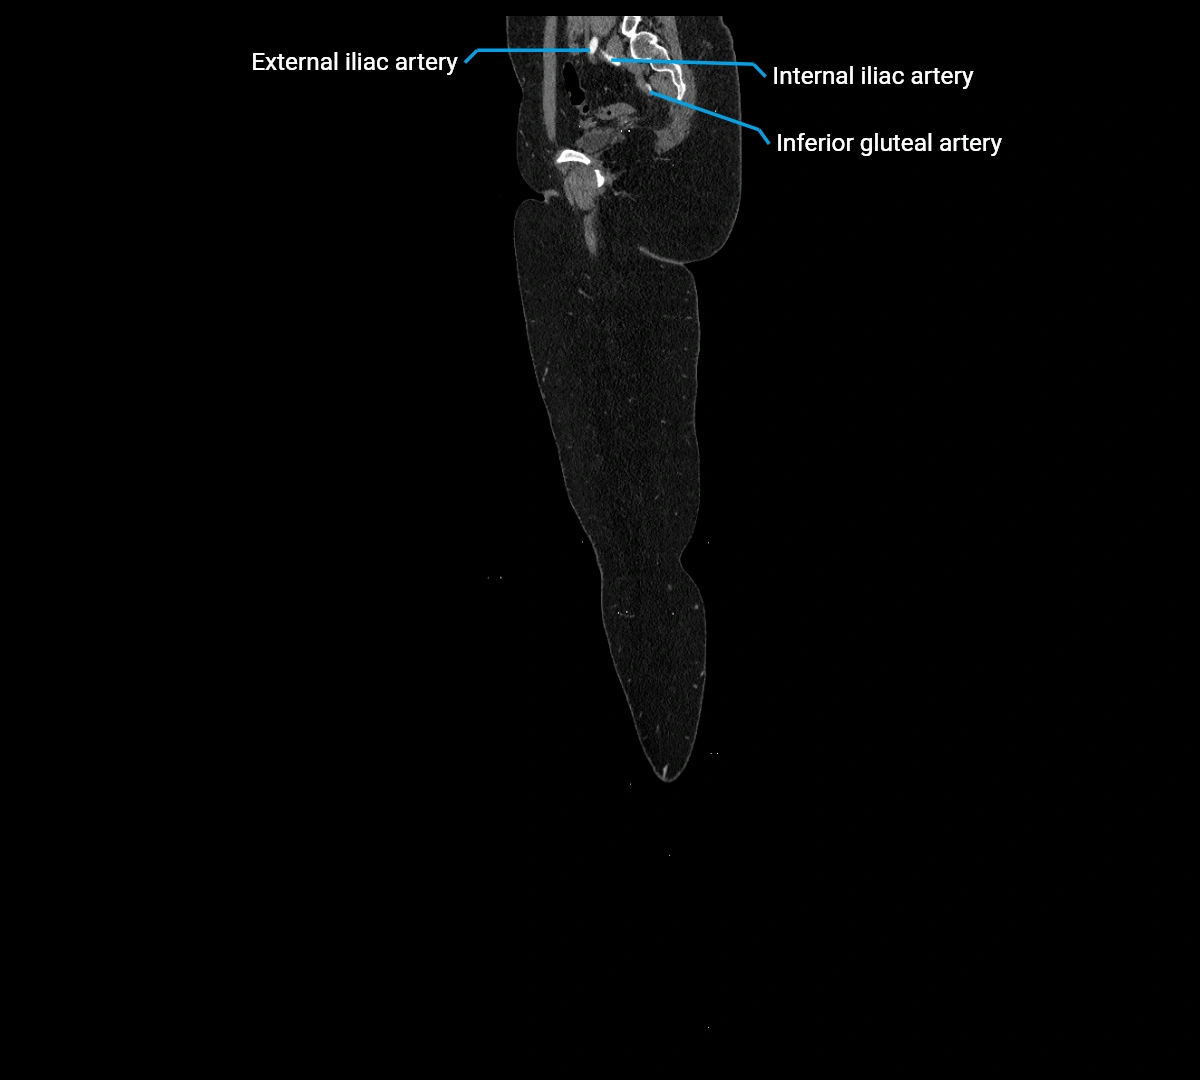

• Terminal branches: right and left common iliac arteries

CT images

image